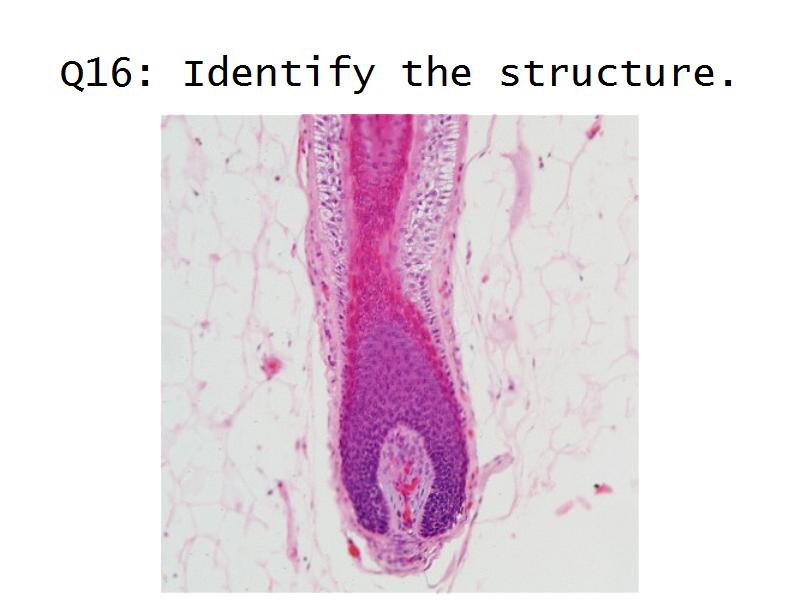

- Basic arrangement of nephrons and collecting tubules in the kidney

- Structure of the nephron and collecting tubules

- Make an annotated diagram of a nephron, including the juxtaglomerular apparatus. Indicate the flow of blood and water in each part, and how solutes are filtered, secreted and reabsorbed.